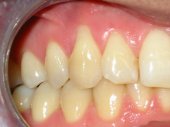

Alteraciones de los tejidos parodontales (encía, ligamento y hueso) por problemas funcionales |

Sangrado gingival espontáneo, infecciones

en las encías o movilidad dentaria debidos al desequilibrio oclusal